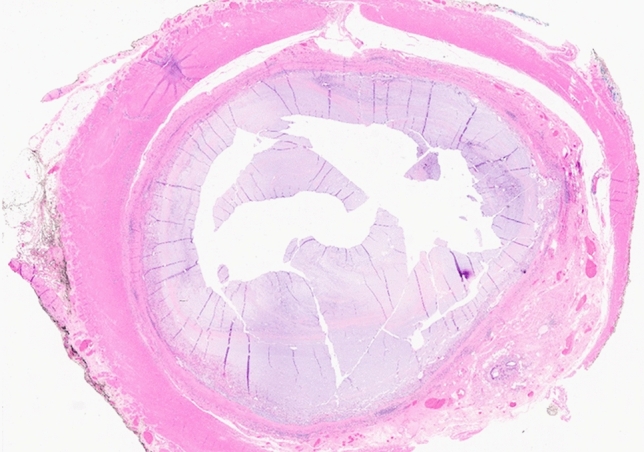

P041